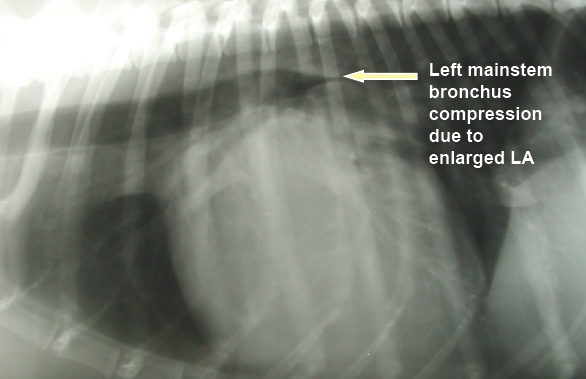

One of the primary calculations which veterinary cardiologists make when gathering data during echocardiographic (echo) scans of dogs' hearts is the LA/Ao ratio (LA ÷ Ao). "LA" stands for the left atrium of the heart, and in this context it is the linear diameter of the left atrium in either millimeters (mm.) or centimeters (cm.). "Ao" stands for the aortic root of the heart, and that is the linear diameter of the aorta artery at its starting point in the left ventricle of the heart, similarly in millimeters or centimeters.

The left atrium (LA) is one of the two chambers of the dog's heart (the

other being the left ventricle) which

enlarge as MVD progresses from just a soft murmur to congestive heart failure

(CHF). If in consecutive echo examinations of the same patient, the

cardiologist finds that the diameter of the LA has increased significantly,

that indicates that the MVD has progressed and the need to medicate the dog

with pimobendan. So, comparing the diameter of the LA in consecutive echo

scans is extremely important information in terms of treating the patient.

However, the aortic root (Ao) of the heart plays no role whatsoever in the progression of MVD. And, most significantly, the diameter of the Ao is not a constant number. It can change so that in one echo scan the Ao's diameter can be x and in a later scan it can be y. Indeed, the condition of the aortic root has been known to change as the dog ages; it deteriorates. So, the size of the Ao when measured when the dog is 5 years old may not be the same as it is when the same dog is examined at age 6 years. In short, it makes no sense to include the Ao measurement in calculations of changes in the dimension of the LA of a single dog.

That said, the LA/Ao clearly has no useful role whatsoever when examining only a single dog's heart to determine if that dog's LA has enlarged between two consecutive echo exams. Since the Ao's diameter can be different in different echo scans of the same dog, when the Ao is included in an effort to determine if only the LA has increased in size, the result completely falsifies the diagnosis. Only if the Ao diameter is constant for all echo scans of that dog -- a very unlikely event -- will the LA/Ao ratio provide any useful information about the size of the dog's LA.

Consider this example: A cavalier King Charles spaniel, already diagnosed

with MVD, has an initial echocardiogram in 2025 showing the LA dimension of

26 mm. and the Ao dimension of 15 mm., resulting in a LA/Ao ratio of 1.73.

An LA/Ao of that size in most cavaliers would indicate that the left atrium

was somewhat enlarged, since normal sized left atriums of cavaliers have a

LA/Ao range from 0.47 to 1.36. So, the cardiologist probably correctly

decides that the LA is enlarged, due to the MVD. On a scale of

"mild/moderate/severe", he categorizes the enlargement as "mild", since he

follows the

ACVIM's 2019 Consensus Statement's erroneous, species-wide definition of

left atrium enlargement as having a LA/Ao of at least 1.6. He prescribes a

starting dosage of pimobendan. He recommends a follow-up echo in 9 to 12

months.

Nine months later in 2026, the same cardiologist, using the same ultrasound equipment, performs a second echocardiogram on the cavalier, in which the LA dimension is 26 mm. (same as the first one) and the Ao dimension is 13 mm. (2 mm. less than the first one), resulting in a LA/Ao ratio of 2.00. The intellectually lazy cardiologist notes that this second LA/Ao, being higher than the first one nine months previously, indicates that the left atrium has continued to enlarge, and that the degree of enlargement now is "moderate-to-severe". He increases the dosage of pimobendan.

The cardiologist ignored the two measurements of just the LA and focused only upon the differences in the LA/Ao ratios in 2025 and 2026. Inarguably, if the question is whether the LA has enlarged since nine months ago, would not comparing only the two measurements of that LA alone give the answer? Obviously, yes!